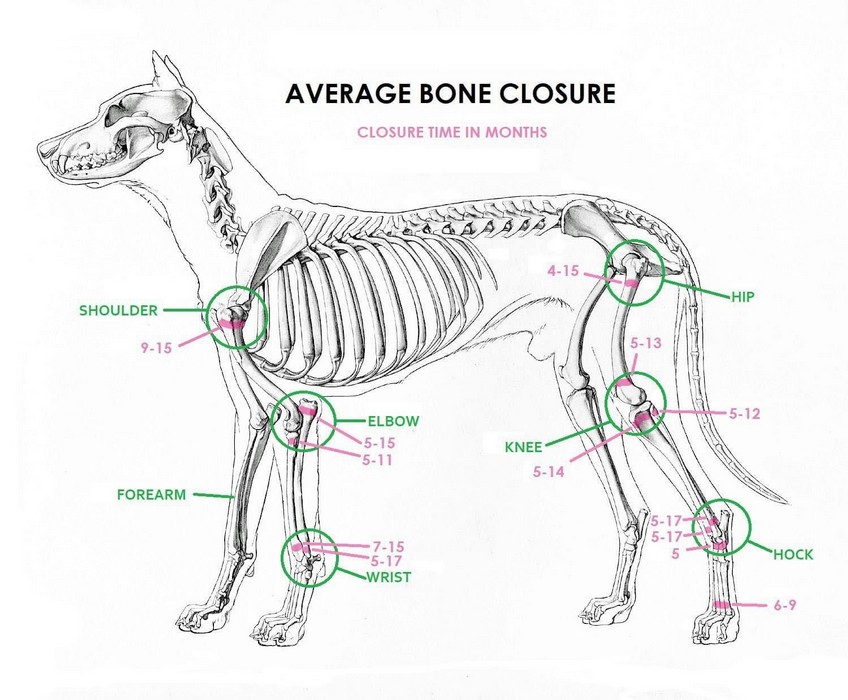

Approximate times of dog joint development lower values apply to miniature and small breeds, higher values to medium and large breeds | ||

HEALTH: Since 1992 we have been doing x-rays of hip and elbow joints Together with Ala Cecrdlova, we were one of the first breeders who pushed for the introduction of the obligation of these health examinations for inclusion among the breeding conditions of retrievers in the Czech Republic. The second health aspect, which we consider very important, is the eye examination. Because we are convinced of itprinciple that the breed, which is most often used as a guide dog, must itself have completely healthy eyes. Our dogs therefore undergo a genetic test for Progressive Retinal Atrophy, Progressive Rod-Cone Degeneration (PRA-prcd). Another genetically tests which our dogs undergo: Centronuclear Myopathy (CNM) Cystinuria, Degenerative Myelopathy (DM) Exercise Induced Collapse (EIC) Hereditary Nasal Parakeratosis (HNPK) Tests of our dogs are sending for evaluation to the DDC DNA Diagnostic Center laboratory in Fairfield, Ohio, USA. Based on the results of these health tests, we then place our dogs in breedin. Also for mating of our females we choose dogs that have also passed genetic tests. Therefore we are able to guarantee future owners that a puppy from us will never get sick with any of the aforementioned genetic defects. We always inform all new owners of our puppies how important a correct and responsible approach to their development is in the first year of life. Because the skeleton and joints - his entire supporting structure - develop up to a year and a half, it is very important to maintain great patience during this period and refrain from overexerting yourself with movement. Proper nutrition is also very important during the development period. To give you a better idea - a puppy in the period up to 18 months will go through the same phase of development as a child up to 15 years old. I.e. for what a human child has 15 years = 180 months for his development, a dog puppy has has only 18 months = 10x less time for his development. That is why it´s very important to maintain a resting regime for a sufficiently long time, especially for larger and giant breeds of dogs. The Labrador, despite being classified as a medium breed, needs, due to its adult weight, the same considerations as large breeds. | ||